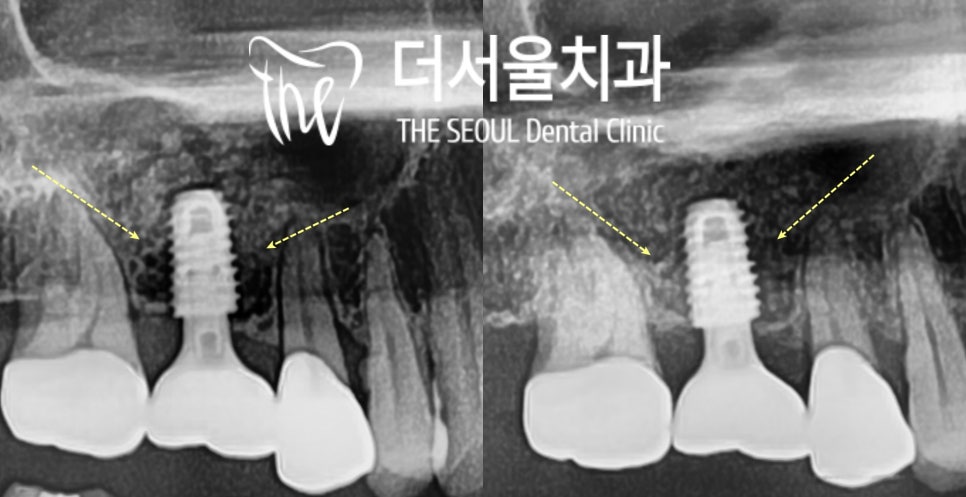

잘보이실지 모르겠는데

자세히 한번 봐보면

하얀색 원기둥모양의 픽스처 주변에

까맣게 비어있던 빈 공간이

조금 하애진거 보이시나요?

시간이 지날수록 그 주변 뼈들이

새로 만들어지면서

점점 더 탄탄하게 고정되가는 것을

확인할 수 있습니다.

뼈가 꽉꽉 찼네요. 만족스럽습니다.